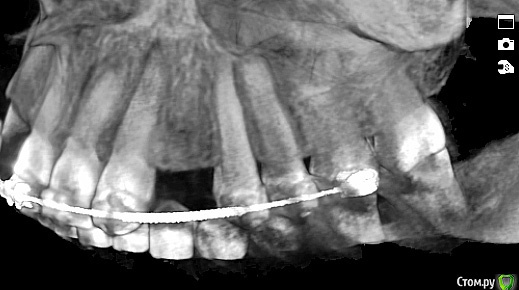

Romanson Опубликовано 13 ноября, 2018 Поделиться Опубликовано 13 ноября, 2018 Здравствуйте.Интересует мнение коллег.Брекеты сняли более года назад.Импланты стоят более года.Как обыграть фронт во втором сегменте? Ссылка на комментарий

Romanson Опубликовано 13 ноября, 2018 Автор Поделиться Опубликовано 13 ноября, 2018 Кроме как превратить клык в двойку и сделать мост 2.2 - 2.4 с клыком вариантов не вижу. Но какой прогноз у такой конструкции?Может кто-нибудь знает другие способы? Ссылка на комментарий